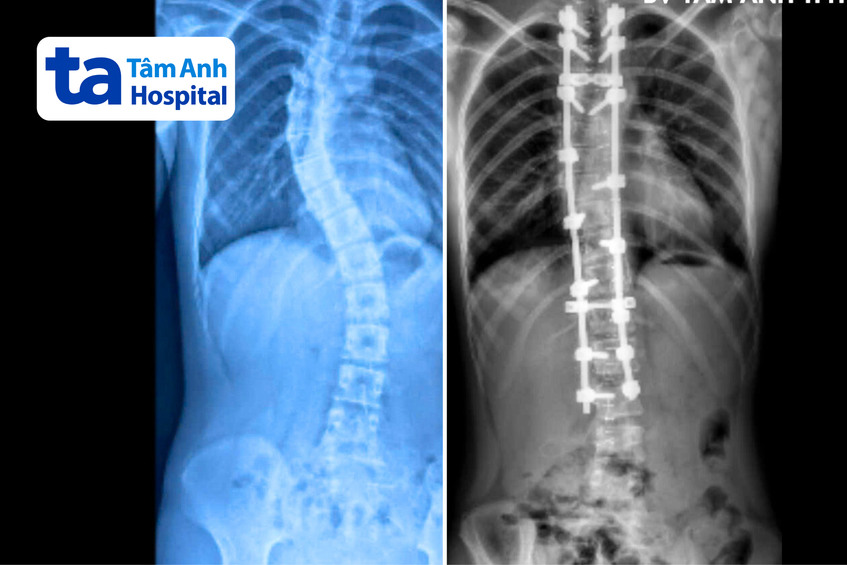

Sophea đã điều trị bảo tồn tại Campuchia trong hơn một năm qua nhưng không có hiệu quả. Kết quả chụp X-quang tại Bệnh viện Đa khoa Tâm Anh TP HCM cho thấy đoạn từ đốt sống ngực thứ 4 đến thứ 10 vẹo sang phải 57 độ, từ đốt sống ngực thứ 10 đến đốt sống lưng thứ 3 vẹo trái 40 độ, có dấu hiệu chèn ép phổi. Quan sát bằng mắt thường có thể thấy hai vai bệnh nhi lệch nhiều, gù lưng.

Ca phẫu thuật kết thúc sau 4 giờ, 16 vít đã được sử dụng để nắn chỉnh phần cột sống trên về 17 độ và cột sống dưới về 15 độ. Ngày thứ 2 sau mổ, bệnh nhi có thể tự đi lại, chiều cao tăng lên, quan sát bằng mắt thường thấy hai vai cân bằng và dáng đi cải thiện rõ rệt. Tiên lượng sau hai tuần, bệnh nhi có thể khôi phục sinh hoạt như bình thường. Khi đó, bệnh nhi được khuyến khích tham gia các môn thể thao như đu xà, bơi lội (tránh các môn có tính đối kháng) và sinh hoạt đúng tư thế để tránh cong vẹo cột sống tái phát hoặc mắc biến chứng đau lưng sau mổ.